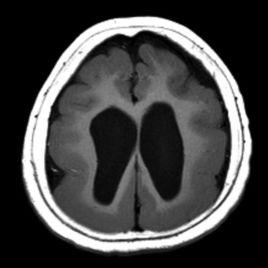

巨腦回畸形的表現為腦回明顯寬大、腦溝淺小、皮層增厚為其主要特徵,可兩側大腦對稱性出現,也可局限一側單獨發生,程度重者腦溝腦回完全消失、腦表面光滑,累及全腦皮質層,也稱為光滑腦或無腦回畸形。

CT和MRI均是現如今診斷巨腦回畸形的主要檢查方法,但MRI具有多序列、多參數、多方位的成像功能,能提供優良的組織解析度和空間解析度,在顯示巨腦回畸形的病理特徵方面比CT有著更大優勢。MRI通過不同加權像上信號的變化和多方位的成像,可以比CT更準確地顯示粗大的腦回、增厚的灰質。對於所合併的顱腦先天畸形,MRI能敏感地發現腦裂畸形的類型,可以更直觀全面地顯示胼胝體發育不良的程度和範圍,清楚顯示多個小腦回畸形的細小腦回和腦溝。